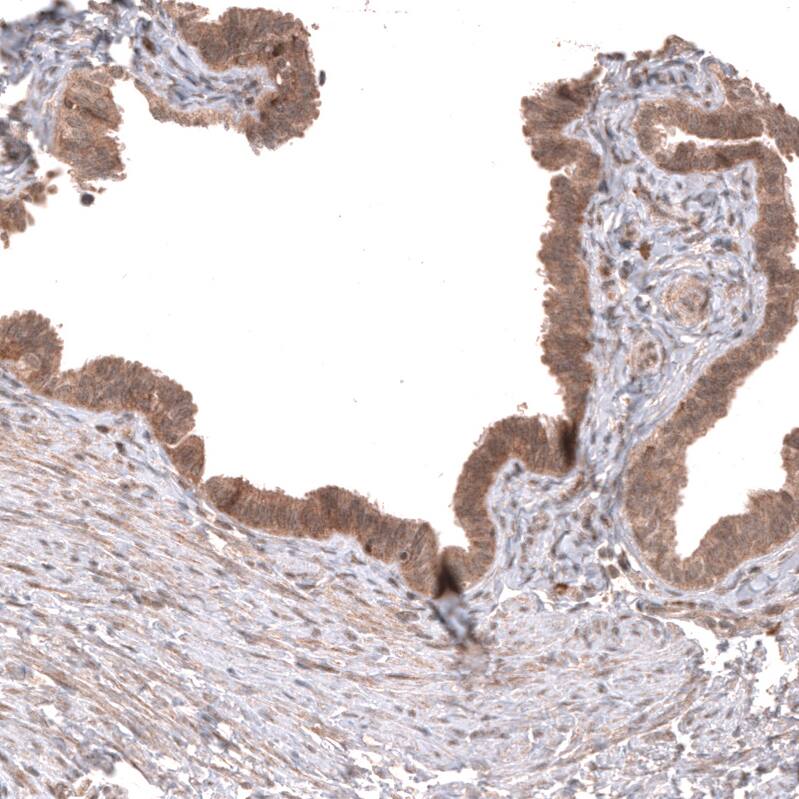

Immunohistochemistry-Paraffin: Wnt-5a Antibody [NBP3-43867]

Staining of human fallopian tube shows moderate cytoplasmic positivity in glandular cells.Immunohistochemistry-Paraffin: Wnt-5a Antibody [NBP3-43867]